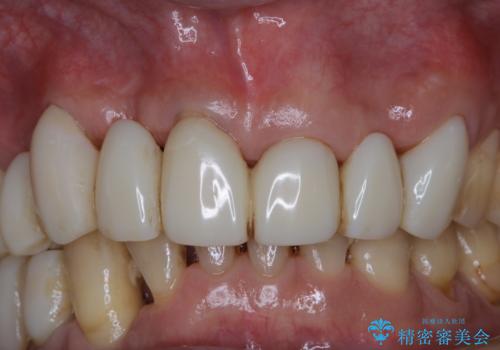

この患者様は、歯科矯正に1、2年かかり矯正中はホワイトニングをすることが出来ないため、歯を白くしてから矯正治療にすすみたいとのことでオフィスホワイトニングを行いました。1回の施術で2.3トーン白くなり、とても白くなりました。ホワイトニングは何度も重ねて白くしていくのですが、1度で満足のいく色見になったため一旦様子を見ることにしました。

1ヶ月後来院して頂きチェックしたところ、やはり後戻りがあったため、再度オフィスホワイトニングを行うことになりました。

1回のオフィスホワイトニングですとこのくらいの後戻りがあるため、ホワイトニングを考えている方は是非参考にしてください。